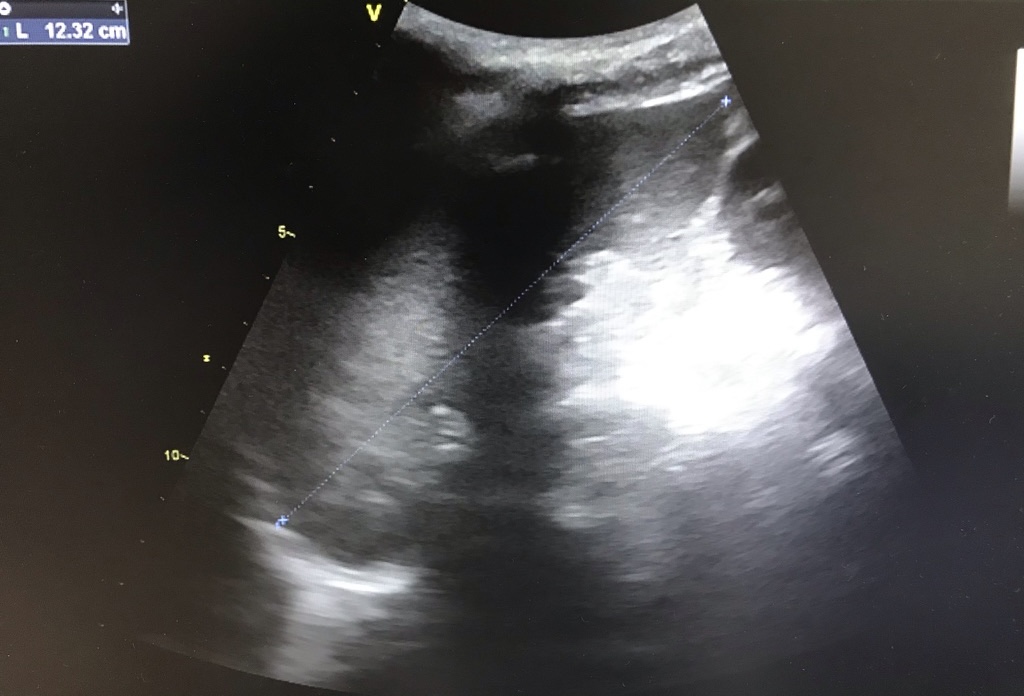

• Anamnesis, exploración física y lugar que ocupa en ella la ecografía: Hombre de 64 años que acude a consulta por astenia e hiporexia, que en los últimos 3 días se han acompañado de náuseas, vómitos y diarrea sanguinolenta. Refiere dolor en vértebras torácicas altas de un mes de evolución. En la exploración física presenta dolor a la palpación en hipocondrio derecho y hepatomegalia de 3 traveses. En consulta se realiza una ecografía abdominales-pélvica

Hallazgos ecográficos

Hepatomegalia con alteraciones difusas en toda la extensión del parénquima hepático de morfología nodular. No se observan otras alteraciones patológicas.